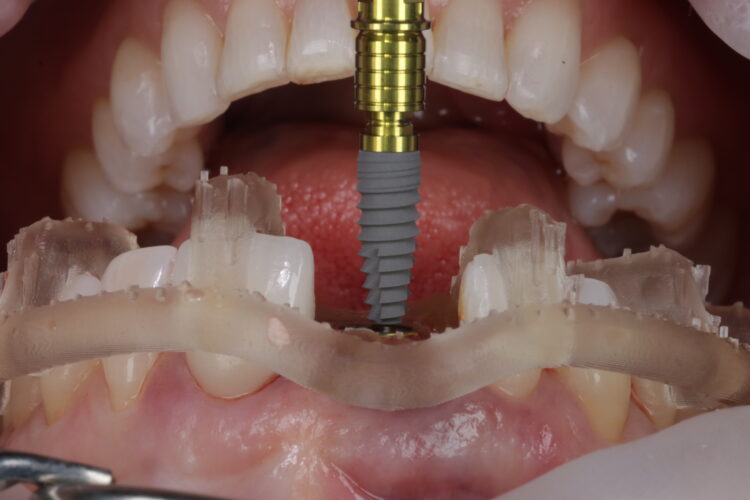

Smile Cloud software with AI-driven smile design features was used to assist treatment planning and provide short animations for use in patient communication. The same data was put into SMOP software to design the surgical guide, which is essential to optimise primary stability for immediate loading.

Two temporaries were requested from the laboratory. One was fabricated from the SMOP guide affording high visualisation to increase precision of fit. The second temporary had a stent that sat over the incisal edges, which could be used to confirm accurate positioning.

The surgical guide was checked in the mouth, ensuring it was fully seating and not in contact with the adjacent teeth.

The standard CONELOG® (BioHorizons Camlog) guided drill sequence was followed. The Guided Surgical Kit is very simple to use with a streamlined number of drills. The CONELOG® drills support primary stability, with side-cutting features and apical threads that engage the native bone.

The CONELOG® Progressive-line implant maximised primary stability and in this case the implant was inserted at 70Ncm. The pre-made temporary was used as the temporary restoration; however, there would also be the option of modifying the existing crown.